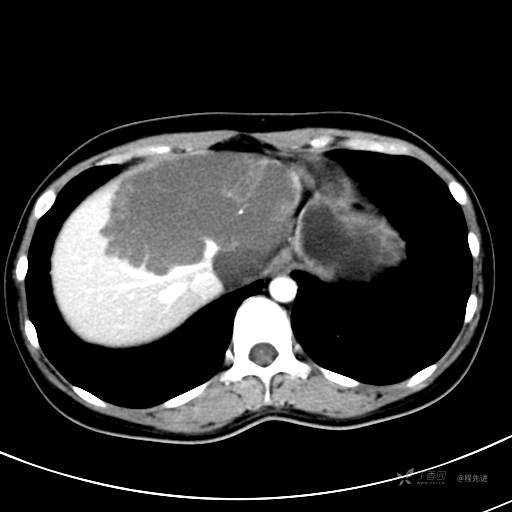

CT平扫+增强,每个序列3张图

CT值 平扫48HU 动脉期66HU 静脉期68HU 延迟期62HU